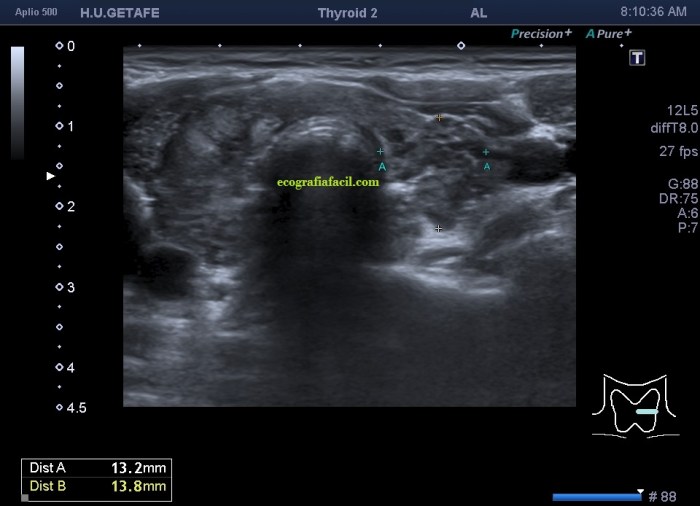

De la imagen 1 a 7 el protocolo habitual, el estudio particular del nódulo con medidas y aplicación del doppler demuestra el aspecto típico del Caballero Blanco.